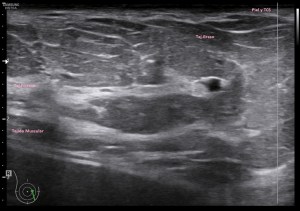

El paciente viene por un bulto en la parte derecha de la espalda, en la región paradorsal alta. Con una sonda de alta frecuencia accedo a la región, que era palpable. Lo primero que observo es que la transmisión del paciente no es buena, esto que a veces pasa que encuentras pacientes, que no sé explicar el motivo, no transmiten bien.

Me da para observar que en la zona de palpación encuentro, profundo en la imagen, un formación hiperecogénica, que está dentro de un músculo. Antes de detallar los hallazgos de la imagen lo que quise fue reconocer bien la anatomía. La piel y el tejido celular subcutánea era muy fácil, también saber que esta anatomía superficial estaba intacta y que la lesión estaba intramuscular, pero me encontraba dos planos musculares, uno superficial, el otro profundo, el profundo con la lesión.

Me tuve que ir al atlas de anatomía para saber cuál era el músculo que estaba debajo del músculo trapecio, que tenía claro que era el superficial. Bien, el músculo que ocupaba el segundo plano en profundidad era el músculo Romboides, que te enlazo para que sepas más de su posición y función.

El protocolo es el típico, cortes en eje corto y largo, con doppler, para comprobar vascularización, como línea roja del lipoma. Imágenes 3,4 y 6.

Después con la radióloga, hicimos una imágenes con «panoramic view» que te dan un detalle de las anatomía con respecto del lado contralateral, sano. Imagen 1.

La lesión era ovalada, hiperecogénica, ocupaba gran parte del músculo, pero respetaba parte de este, que era hipoecogénico (imagen 5), recuerda que así es por definición y que ésta ecogenicidad del músculo es referencia para el resto de ecogenicidades del aparato locomotor. Como te he contado, no había doppler color ni en modo angio.